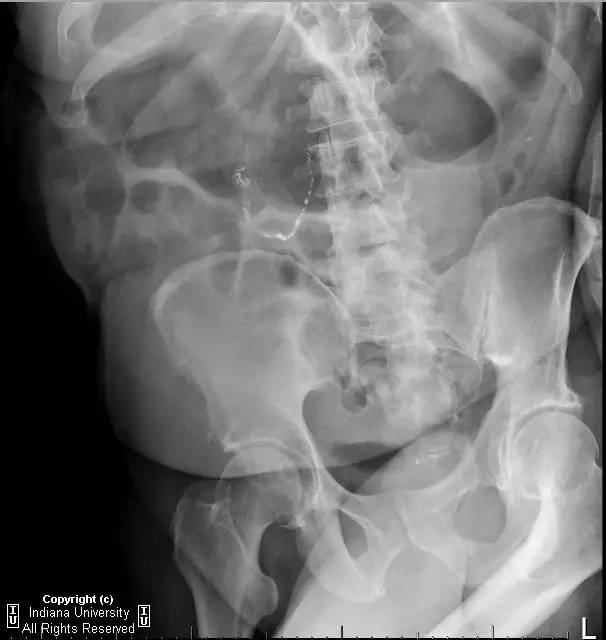

【病史】男性,腹胀。

问题1.如果存在肠梗阻,最可能的部位为?

注意右下腹弯曲串珠样密度影,你的考虑可能为?

2.横结肠扩张的原因为?

3.X线片弯曲串珠样密度影最可能为?

【答案】1.A 2.E 3.C

【影像学表现】右侧腹部可见曲线样不透亮区,1周后位置有变化(似进入盲肠)。横结肠显著扩张、充气。CT上扩张原因不明,无明确的梗阻证据。

【诊断】阑尾内对比剂充填